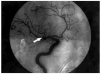

El ECG inicial, realizado en el servicio de urgencias, puso de manifiesto un ritmo sinusal de 80 lat/ min, con un QTc de 384 ms y datos de lesión subepicárdica anterior con elevación del ST más marcada en V2-3, I y aVL y descenso del ST en III y aVF (fig. 1, ECG 1). La tomografía axial computarizada (TAC) realizada a su ingreso objetivó una HSA de predominio en la cisura silviana derecha y en la arteriografía realizada a las 16 h se visualizó un aneurisma de 5 mm de diámetro en la bifurcación de la arteria silviana derecha (fig. 2).

Fig. 2. Arteriografía cerebral: aneurisma de 5 mm de diámetro (flecha) en la bifurcación de la arteria cerebral media derecha.